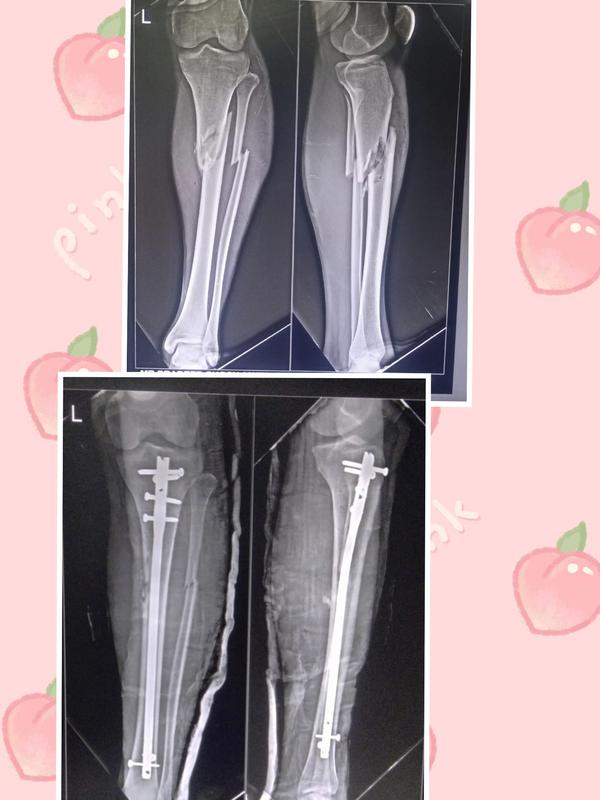

20 year old male with road traffic accident sustai...